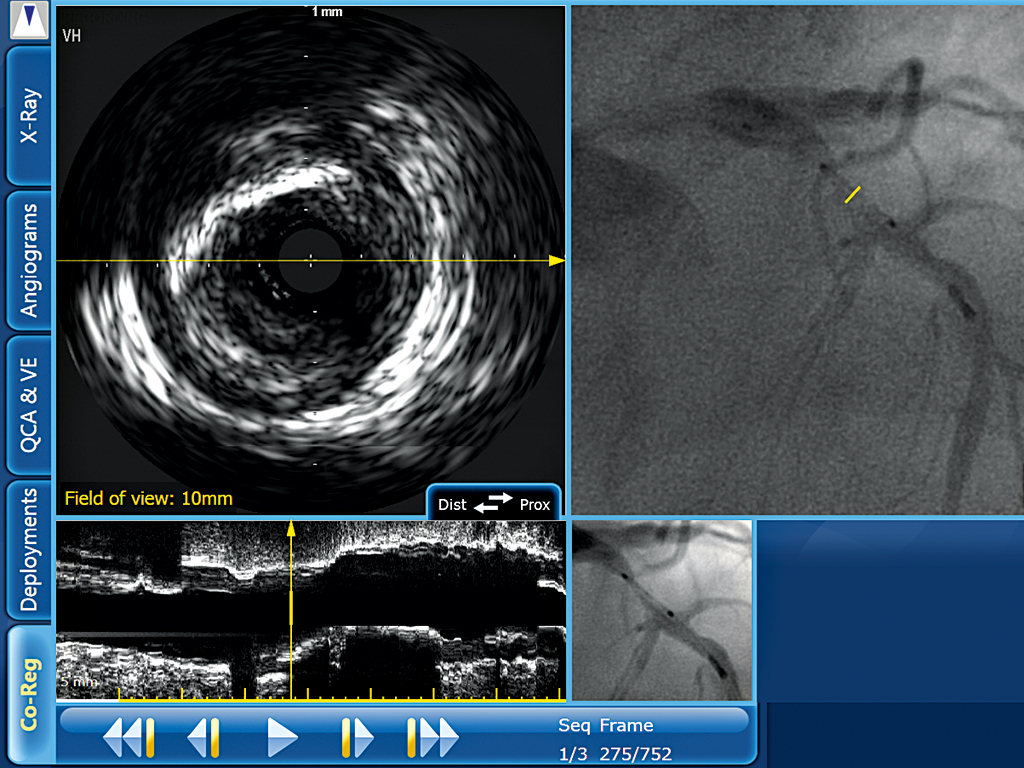

A screengrab from SyncVision, Volcano’s online image processing workstation. The company has invested heavily in developing imaging techniques to reduce heart disease

The IVUS technique gives physicians an incredibly detailed insight into plaque build-up in coronary arteries that was impossible to achieve with traditional methods. “The IVUS modality is camera-mounted on a catheter support with a diameter of less than 1.5mm. It provides a precise anatomical perspective from inside the coronary artery, with a 360° view. In addition to the traditional, high-resolution, grey-scale IVUS image, the virtual histology feature provides colour-coded information to characterise the nature of the plaque; it is thus possible to recognise a stable plaque or a risk of plaque rupture.”

Volcano has recently launched a new product that combines angiogram recordings with IVUS images: SyncVision, an online image processing workstation for coronary vessels that allows physicians to simultaneously navigate on both an angiogram and an IVUS image in a single correlated view. SyncVision is designed to combine the functionality of the angiographic road map with the precision of the intra-vessel IVUS image and simplify the procedure for interventionalists.